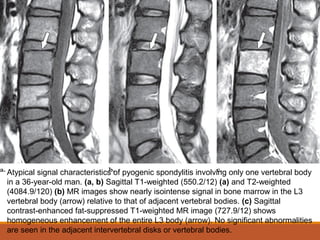

Atypical signal characteristics of pyogenic spondylitis involving only one vertebral body

in a 36-year-old man. (a, b) Sagittal T1-weighted (550.2/12) (a) and T2-weighted

(4084.9/120) (b) MR images show nearly isointense signal in bone marrow in the L3

vertebral body (arrow) relative to that of adjacent vertebral bodies. (c) Sagittal

contrast-enhanced fat-suppressed T1-weighted MR image (727.9/12) shows

homogeneous enhancement of the entire L3 body (arrow). No significant abnormalities

are seen in the adjacent intervertebral disks or vertebral bodies.